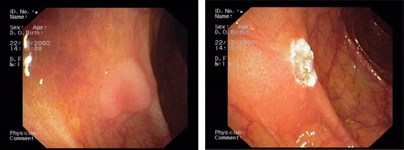

imagen3

Úlcera rectal múltiple